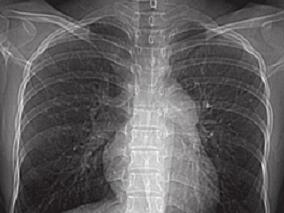

1小时条评论患者,女,33岁。近两年来查出HIV阳性,这次因活动后气短加重伴下肢水肿来院就诊。患者患有哪些疾病?详见以下病例 【临床资料】 患者,女,33岁。因活动后气短8年,加重伴下肢水肿2个月入院。8年前出现剧烈活动后气短,此后体力活动耐力逐渐下降,2008年在当地医...